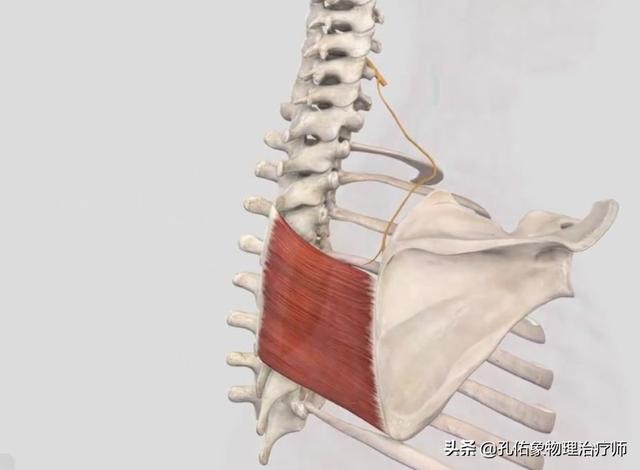

La première raison est quePiégeage du nerf scapulaire dorsalRésultat. Le nerf scapulaire dorsal innerve principalement les muscles scapulaire et rhomboïde juste après la naissance.La région du bord médial de l'omoplate est située à l'endroit où s'attache le muscle rhomboïde, comme le montre l'illustration ci-dessous :

Le nerf dorsal de l'omoplate est innervé par le nerf cervical 5. Par conséquent, si une personne a une mauvaise colonne cervicale, en particulier s'il y a un problème avec l'espace vertébral cervical 4-5 ou une hernie discale dans la colonne vertébrale cervicale 4-5, le nerf cervical 5 sera comprimé, ce qui provoquera une douleur dans la zone du bord médial de l'omoplate.

Un tel physique affectera directement le fascia rhomboïde attaché à l'omoplate dans le dos, vous voyez où les rhomboïdes se développent ?

Comme indiqué ci-dessus, le muscle rhomboïde est composé de deux parties, le petit muscle rhomboïde en haut et le grand muscle rhomboïde en bas, qui partent tous deux de l'apophyse épineuse sur la ligne médiane de la colonne vertébrale jusqu'au bord médial de l'omoplate. C'est par l'aspect du physique décrit ci-dessus que leLes rhomboïdes sont ensuite étirés sur les côtés, comme si l'on tirait sur un sac en plastique, et à un certain moment, une douleur apparaît dans la zone du bord médial de l'omoplate.L'arrière des épaules et l'arrière du corps ressentent comme un poids lourd. En même temps, vous aurez une sensation d'enfoncement et de lourdeur à l'arrière des épaules, comme si vous portiez une lourde charge sur votre dos ; et bien sûr, les rhomboïdes sont souvent faibles parce qu'ils ont été étirés pendant longtemps.Une omoplate à aile externe dont le bord médial fait saillie vers l'extérieur.Les femmes prédominent.